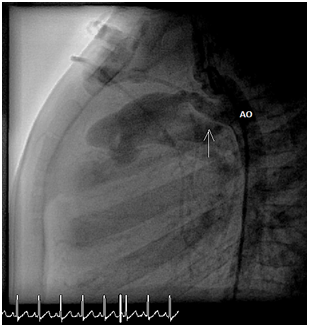

After waiting a few minutes the angiography showed PDA 2mm, with length 9mm (Figure 4).

Figure 4 Angiogram showed the PDA (black arrow).